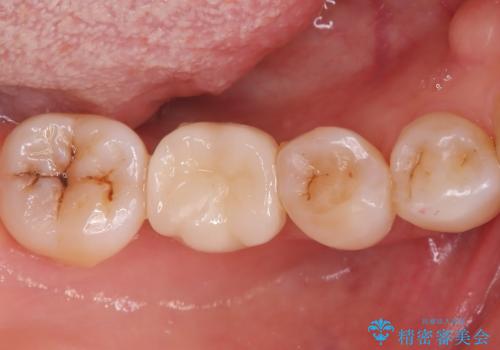

奥歯に虫歯があると言われた セラミッククラウンでキレイで長持ちする歯へ

担当医 榊原康平